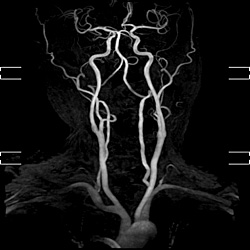

頚部MRA